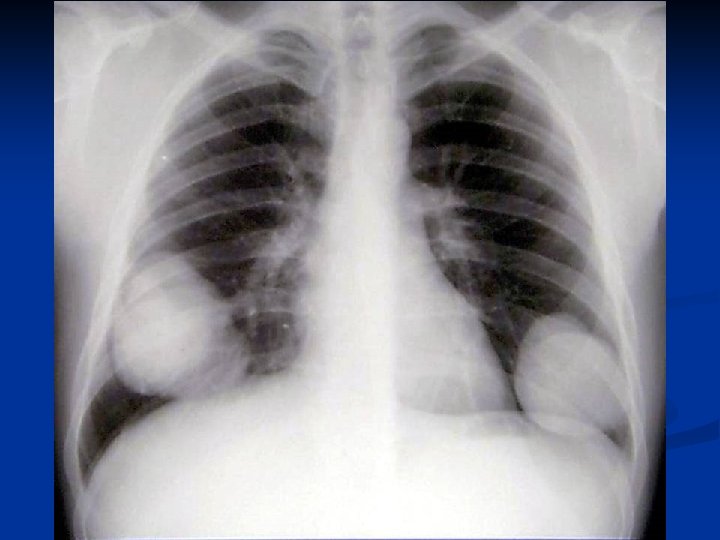

Distributie in functie de numarul localizarilor

Asociere CHP cu CHH